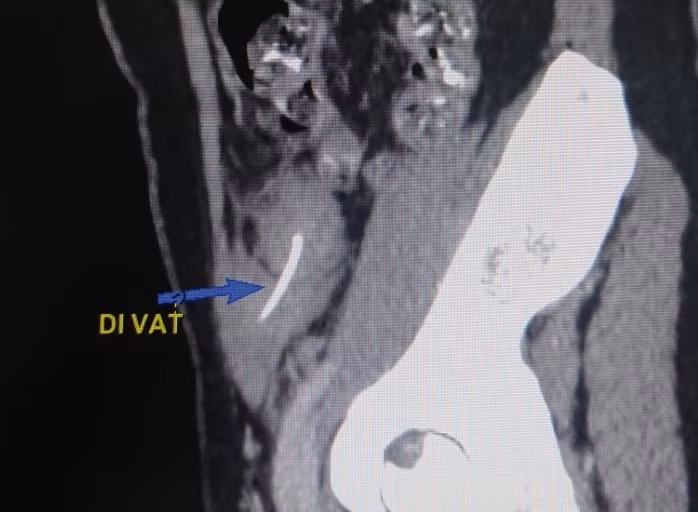

Chụp CT bụng có cản quang ghi nhận hình ảnh dị vật cản quang dạng xương cá đâm xuyên qua thành quai ruột non vùng hố chậu.

Bệnh nhân được chỉ định phẫu thuật nội soi cấp cứu. Ê-kíp phẫu thuật tiến hành bóc tách khối viêm ở thành bụng, hố chậu trái có khối viêm dầy kích thước 3x4cm được mạc nối lớn bám. Phẫu tích khối viêm ở thành bụng, cắt mạc nối lớn lấy một dị vật xương cá dài 3cm. Cắt khối viêm và mạc nối lớn làm giải phẫu bệnh. Ca phẫu thuật diễn ra thành công sau 1 giờ.